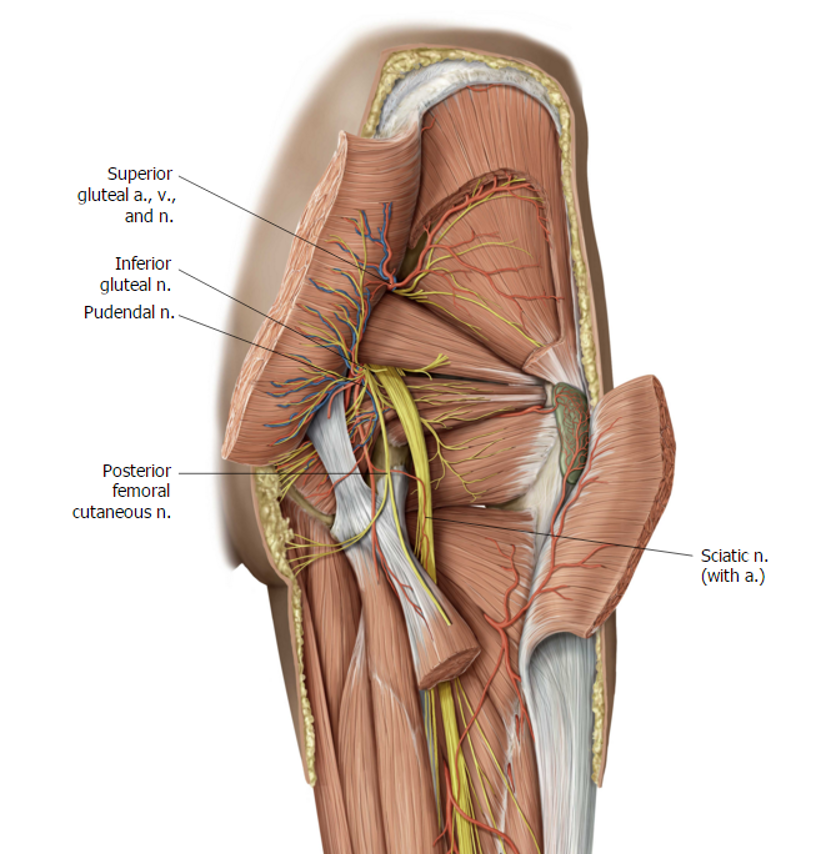

what causes Piriformis Syndrome?

Sitting for long periods of time – “wallet neuritis” or “fat wallet syndrome” (ie nerve compression from sitting on a wallet)

what are safe site of injections for Intragluteal Injections

superolateral quadrant of the gluteal region

anterolateral thigh in tensor fascia latae

Trendelenburg Sign

is indicative of what type of n injury?

superior gluteal n. injury

Hip drop – abductors are not activating – muscle is paralyzed